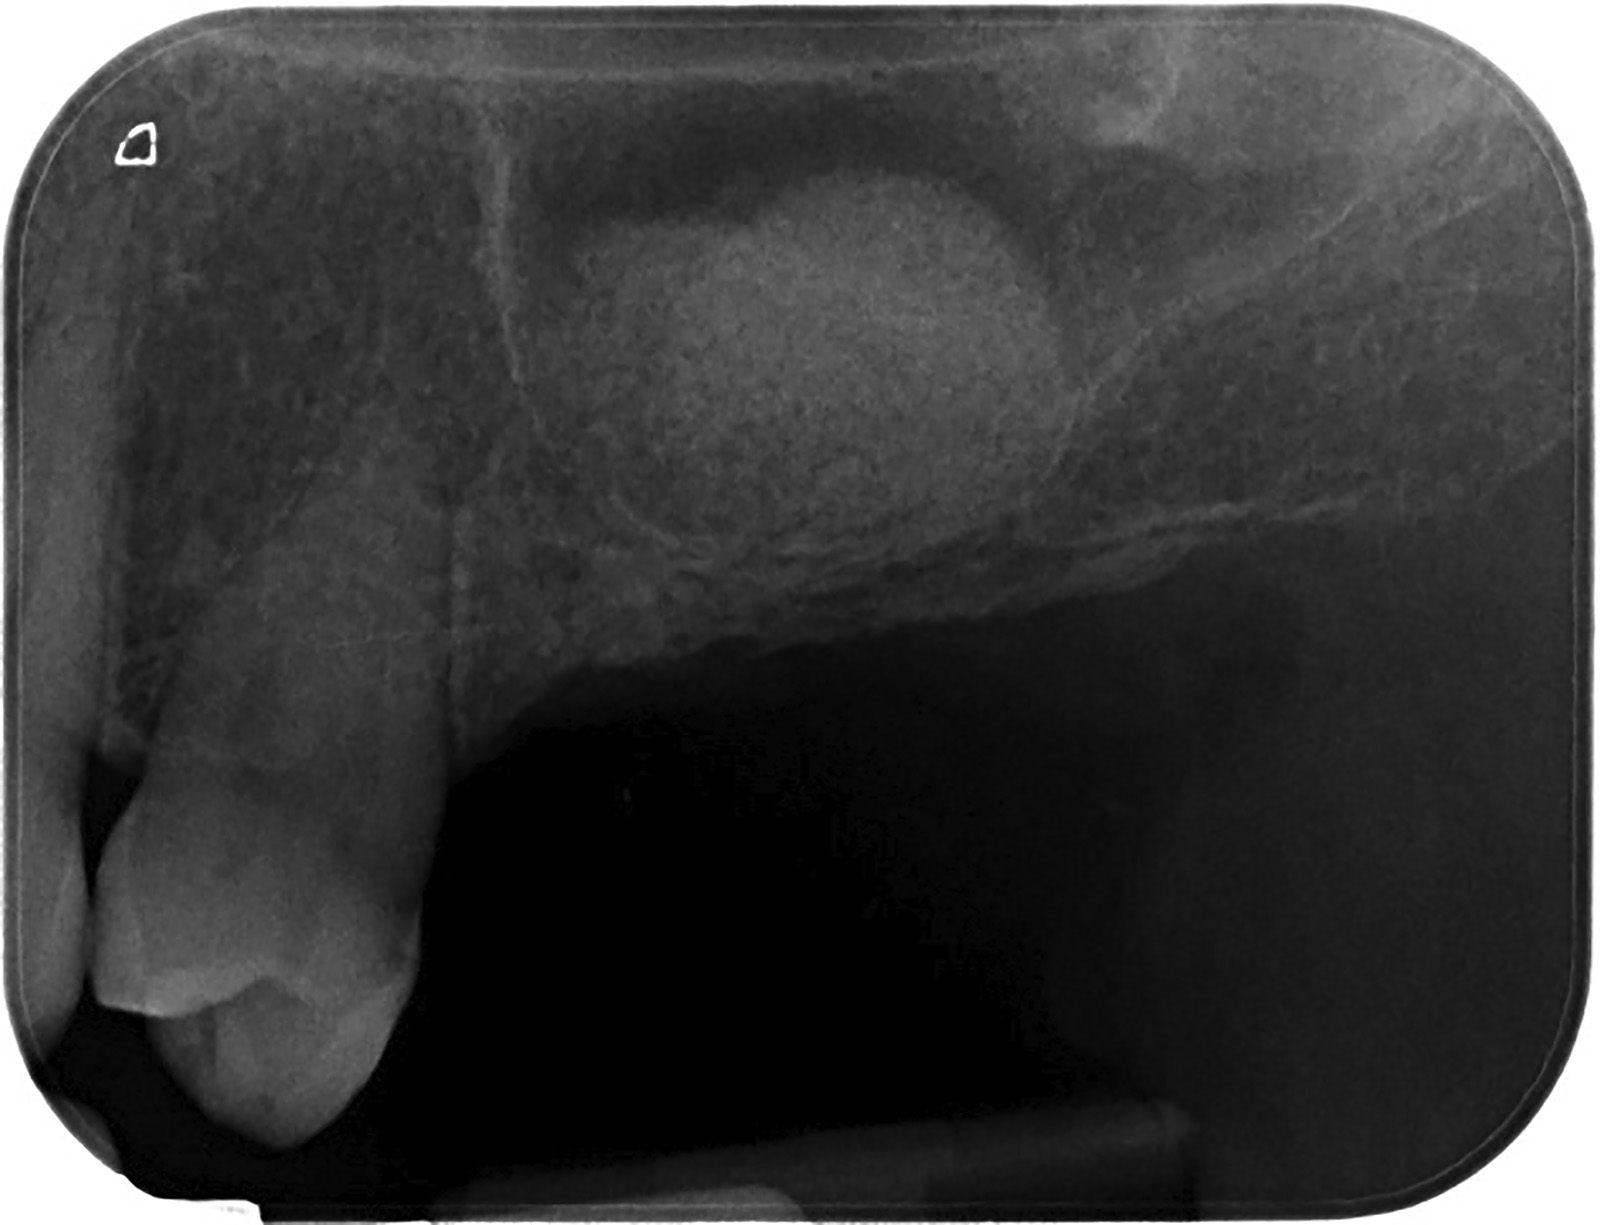

PREMESSA: in seguito all’estrazione dell’incisivo laterale superiore di destra, resasi necessaria per cause batteriche, si decide di affrontare il caso con il posizionamento di un impianto in sostituzione dell’elemento mancante dopo guarigione del sito infetto. Con tecniche rigenerative sia dei tessuti ossei mancanti a causa dell’infezione pregressa, sia dei tessuti gengivali che appaiono inizialmente troppo spostati in alto, si ripristina una corretta morfologia delle parabole (contorni) gengivali e delle papille interdentali (triangoli di gengiva tra due denti vicini).